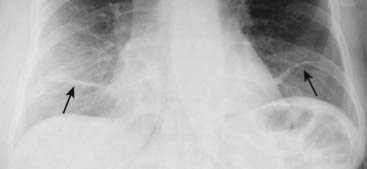

Figure 5-7 Subsegmental atelectasis.

Close-up view of the lung bases demonstrates several linear densities extending across all segments of the lower lobes, paralleling the diaphragm (solid black arrows). This is a characteristic appearance of subsegmental atelectasis, sometimes also called discoid atelectasis or platelike atelectasis. The patient was postoperative from abdominal surgery and was unable to take a deep breath. The atelectasis disappeared within a few days after surgery.